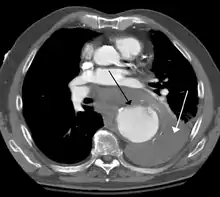

Contrast enhanced CT of a ruptured large (7 cm) thoracic aneurysm, with black arrow indicating the aorta, and white arrow blood in the thorax

The principal causes of death due to thoracic aneurysmal disease are dissection and rupture. Once rupture occurs, the mortality rate is 50–80%. Most deaths in patients with Marfan syndrome are the result of aortic disease.